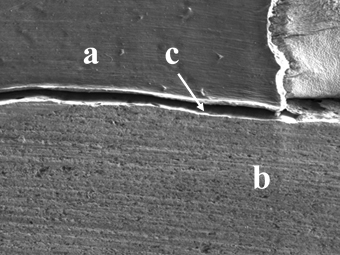

Полученные образцы зубов были исследованы с помощью растрового электронного микроскопа в области соединения композитного материала с боковыми стенками и дном сформированной полости зуба под 100-кратным увеличением (см. рис. 1, 2, 5, 6, 9, 10 с условными обозначениями на рисунках, где а — композитный пломбировочный материал, б — стенки зуба, в — зона соединения композитного пломбировочного материала со стенками зуба, которая могла быть представлена либо в виде щели, как на рис. 1, 2, 5, 6, либо в виде плотного соединения с отсутствием зазора, как на рис. 9, 10). Так же эти зоны были исследованы под 1500 кратном увеличением (см. рис. 3, 4, 7, 8, 11, 12 с условными обозначениями, где а — композитный пломбировочный материал, б — стенки зуба, в — зона соединения композитного пломбировочного материала со стенками зуба, которая могла быть представлена либо в виде щели, как на рис. 3, 4, 7, 8, либо в виде плотного соединения с отсутствием зазора, как на рис. 11, 12). При таком увеличении при наличии щели проводилось измерение ее ширины между композитным материалом и стенками зуба в местах с максимальным размером в пределах поля зрения с точностью 0,001 мкм (рис. 3, 4, 7, 8). Эти данные вносились в сводную таблицу для проведения статистического анализа.

В 3-й группе были получены результаты от 0 до 5,785 мкм (рис. 9–12; см. таблицу). Стоит отметить, что это единственная группа, в образцах которых были срезы с полным отсутствием щели в зоне соединения пломба-ткани зуба в поле зрения микроскопа.

В 3-й группе средний размер щели был меньше, а в некоторых образцах они вовсе отсутствовали (см. рис. 11, 12; см. таблицу), что свидетельствует о том, что физическое воздействие на неполимеризованный композит, такое как нагрев и вибрационное воздействие, влияет на качество краевого прилегания.